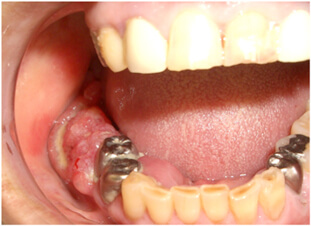

舌がん

口腔がんの中でもっとも多いものです。

舌の脇(舌縁)に多く発生します。誤って舌を噛んでしまったり、あわない入れ歯があたっていたり、むし歯を治療せずにたえず舌に傷をつくったりすることがきっかけになることがあります。